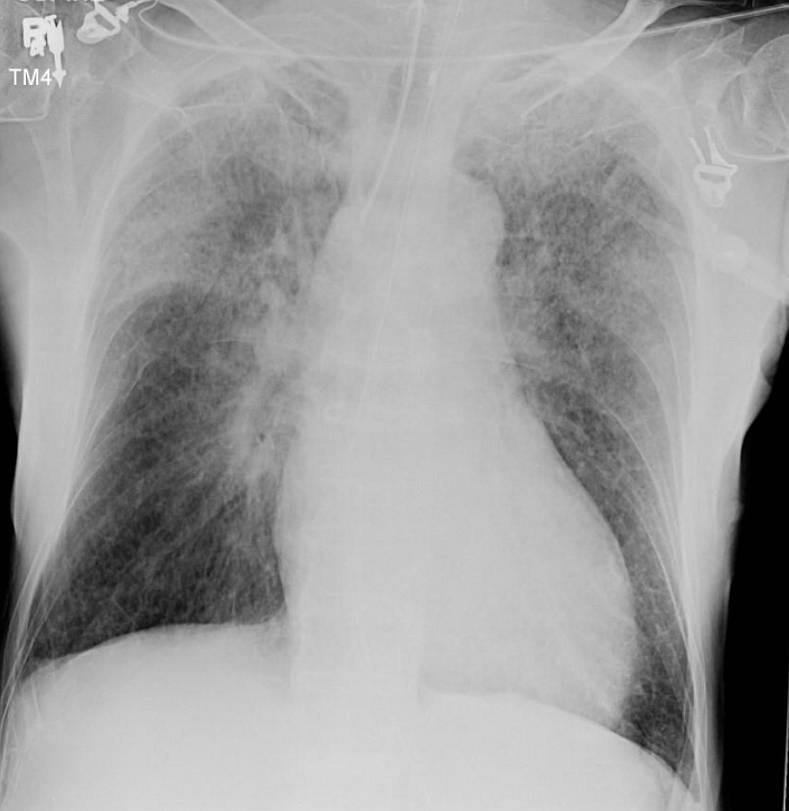

A 68-year-old male patient presented with decreased level of consciousness. A non-enhanced trans-axial head CT was obtained showing a hypertensive left cerebellar haemorrhage and subarachnoid extension.

What changes are noted on the chest x-ray and what’s the diagnosis ?